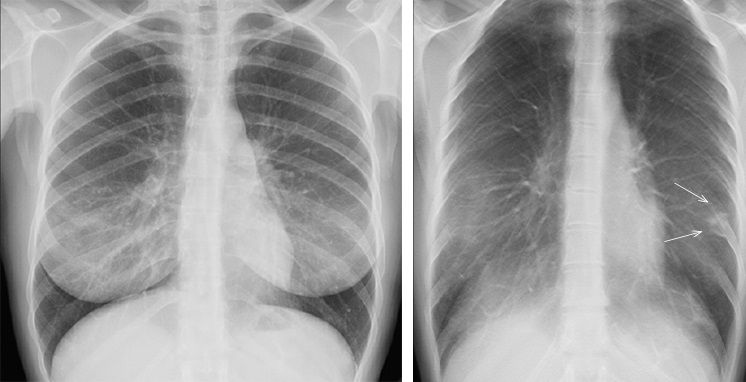

Así, estos investigadores proponen una herramienta de diagnóstico adicional para Covid-19 que proviene de las imágenes de los pulmones. Para el diagnóstico de las enfermedades pulmonares, las radiografías de tórax o las tomografías computarizadas son los principales recursos, y pueden utilizarse para distinguir la Covid-19 de otros tipos de lesiones pulmonares, así como para evaluar la gravedad de la afectación pulmonar en la Covid-19. Estos tipos de imágenes pueden mejorar la capacidad de diagnóstico de los pacientes con Covid-19, especialmente si se combinan con modelos de inteligencia artificial.

Para ello, los investigadores empezaron por utilizar un modelo para recoger automáticamente datos de imágenes de los lóbulos pulmonares. A continuación, se analizaron estos datos para obtener características como posibles biomarcadores de diagnóstico de Covid-19. Estos biomarcadores de diagnóstico mediante el modelo de inteligencia artificial se utilizaron posteriormente para diferenciar a los pacientes con Covid-19 de los pacientes con neumonía y de los sanos.

El modelo completo se desarrolló con una cohorte de 704 radiografías de tórax y, a continuación, se validó de forma independiente con 1.597 casos procedentes de múltiples fuentes compuestas por pacientes sanos, con neumonía y con Covid-19. Los resultados mostraron un excelente rendimiento del modelo a la hora de clasificar los diagnósticos de los distintos pacientes.